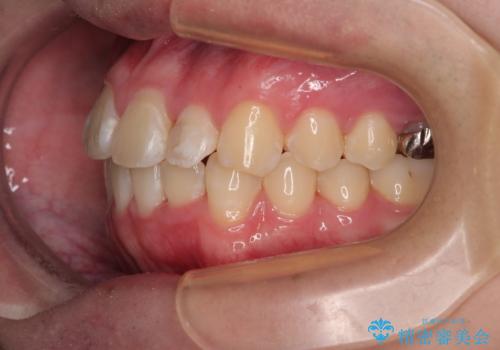

適切な診断と装置の選択により、1年という短期間でここまで改善できます。

見た目の美しさだけでなく、将来のむし歯や歯周病リスクを減らすことにもつながる治療です。